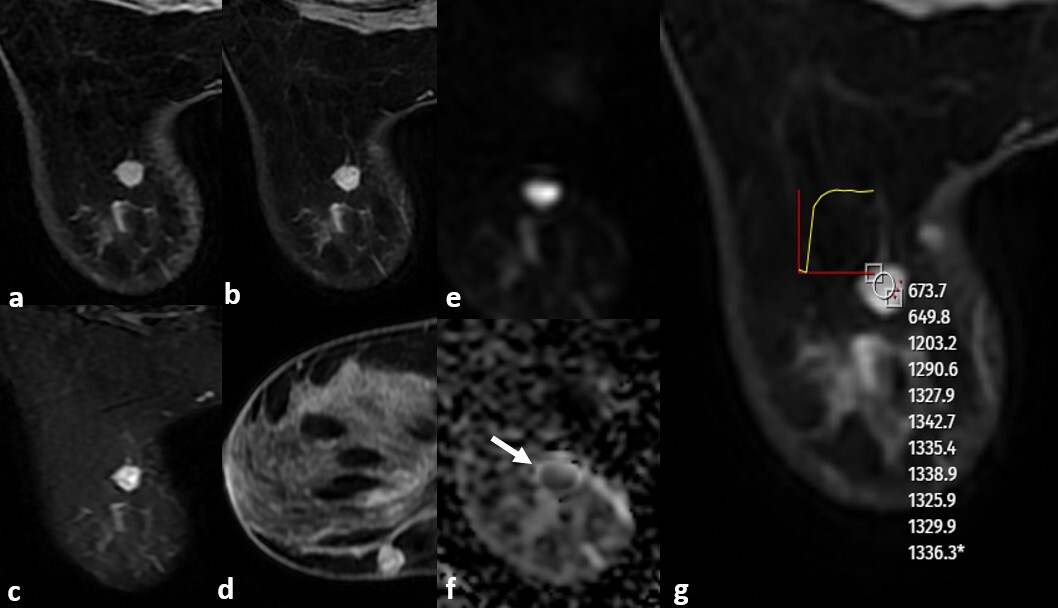

Figure 2

An 8 mm diameter, well-defined, round lesion visible on magnetic resonance imaging of a 40-year-old female patient who presented for a routine breast examination, showing contrast-enhanced (A) and non-contrast-enhanced axial and sagittal (B, D) T1-weighted images. The lesion showed heterogeneous enhancement on T1-weighted images, was hyperintense on fat-suppressed T2-weighted images (C), demonstrated diffusion restriction on diffusion-weighted imaging (E, F), and exhibited a plateau enhancement pattern on dynamic contrast-enhanced T1-weighted images (G). The Kaiser score was assessed as 2. Core needle biopsy revealed luminal A, HER2-negative Grade 1 invasive ductal carcinoma